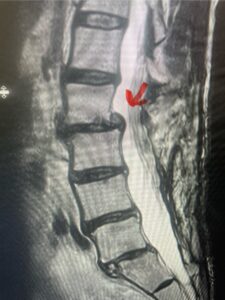

This 61-year-old female with a history of severe osteoporosis and a prior history of a laminectomy from l2-S1 with an L5-S1 instrumented fusion, presents with progressive low back pain and right lower extremity radiculopathy. MRI revealed a grade 1 L2-3 spondylolisthesis with severe stenosis mainly from severe right L2-3 facet joint hypertrophy which was compressing the right L3 descending nerve root. (Fig. 1). She had failed conservative management consisting of physical therapy and pain management with epidurals. She underwent an L1-3 revision laminectomy where we had to dissect a plane underneath the inferior aspect of the L2 lamina. We performed an instrumented fusion at L2-3 with special hydroxyapatite-coated screws to improve fixation to surrounding bone given here severe osteoporosis (Fig. 2) This worked out well and the patient had an uneventful recovery with relief of her leg pain.

Figures 1a: Sagittal and axial T2-weighted lumbar MRIs demonstrating a grade 1 L2-3 spondylolisthesis (red arrow) with severe stenosis secondary to right L2-3 facet hypertrophy (red arrow).